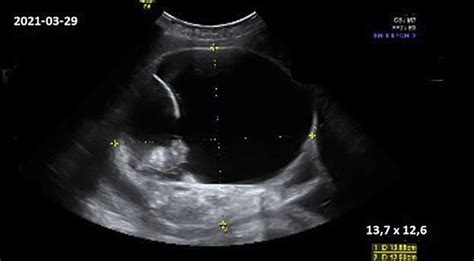

Nuo pirmosios paskutinių mėnesinių dienos praėjus 11-13 nėštumo savaitėms, atliekamas detalus ultragarsinis tyrimas. Nustatoma preliminari gimdymo data. Apžiūrimos pagrindinės kūno dalys, smegenų struktūra, ieškoma chromosominėms genetinėms ligoms būdingų žymenų. Bene svarbiausias rodmuo - vadinamosios sprando raukšlės (kitaip - vaiskumo) matmuo.

Akušerinė echoskopija atliekama vaisiaus ir akušerinės patologijos, vaisiaus raidos ydų diagnostikai. Nėra duomenų apie žalingą diagnostinio ultragarso poveikį vaisiui. Jam kontraindikacijų nėra. Nėščiosioms rekomenduojama atlikti 1-2 ultragarsinius tyrimus, jei nėra papildomų indikacijų. Moksliniais įrodymais pagrįstais duomenimis, ultragarsinis tyrimas antrąjį nėštumo trimestrą yra svarbus vaisiaus anomalijoms, nėštumo trukmei nustatyti, vaisiaus biometrijai atlikti.